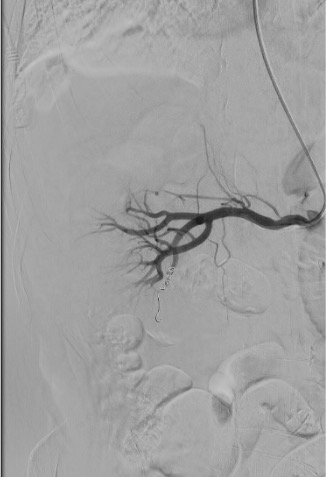

Completion Angiogram

- Renal infarction — expected consequence of segmental artery embolization (end-arteries); superselective technique limits infarction to <10% of parenchyma in best cases

- Coil migration — occurs in <2% of cases; retrievable with endovascular snare

- Incomplete embolization — recurrent bleeding; usually apparent on completion angiogram; additional embolization required

- Superselective embolization results in <10% non-target parenchymal infarction

- Technical success rate for emergent renal artery embolization: ~93%